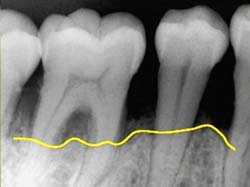

Etapas de la Gingivitis

Con todo esto quiero que tomen conciencia que la tristemente famosa piorrea, no sólo afecta el apoyo de los dientes en el hueso maxilar haciendo que estos se aflojen y se pierdan, con la consecuente pérdida de función masticatoria y de estética, sino que puede producir enfermedades generales o agravar las ya existentes.